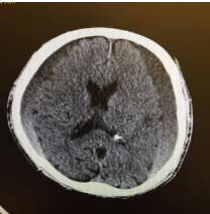

Fig 1,2,3,4,5,6,7,8,9,10,11,12,13,14,15

Figure 3

Figure 4